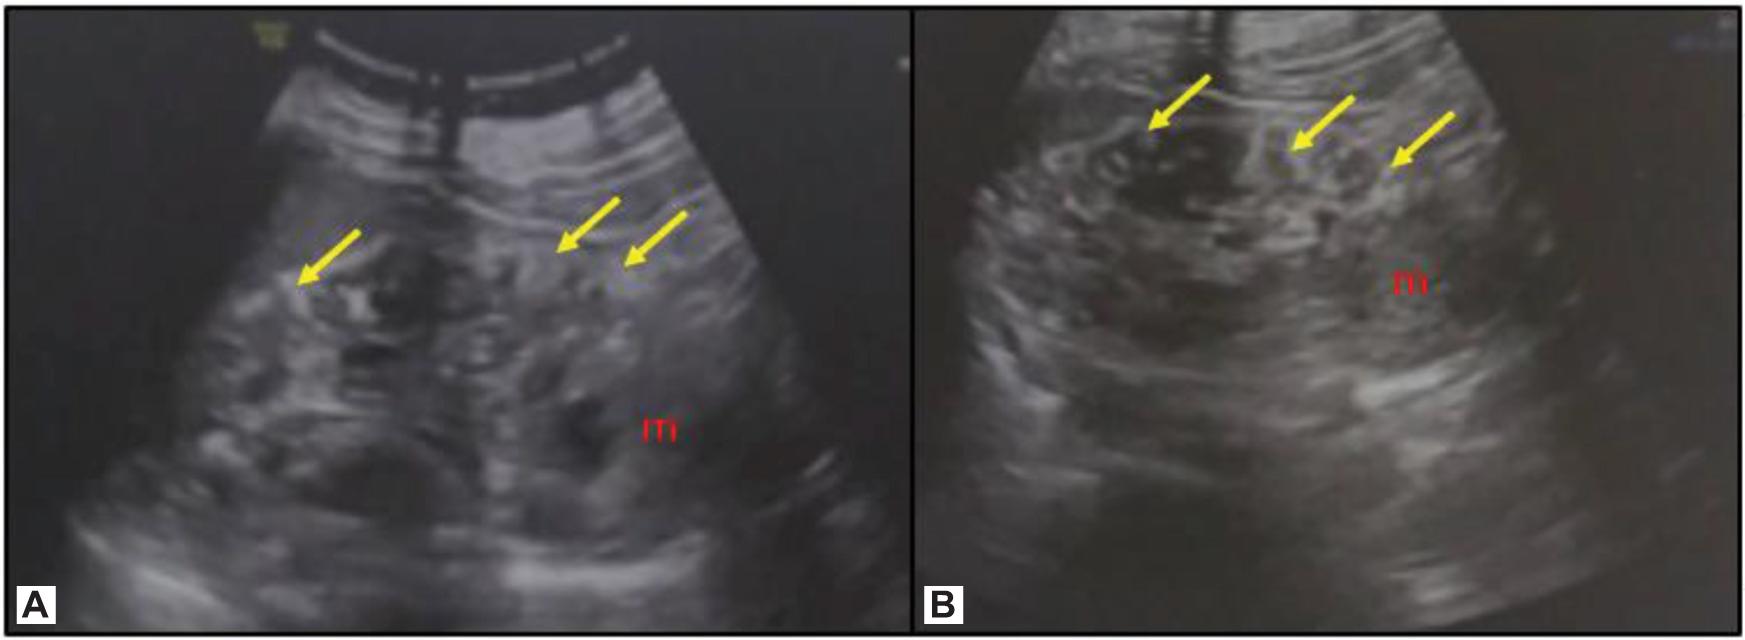

An abdominal ultrasound revealed multiple well-defined elongated echogenic focal lesions close to the cortex in the right and left kidney, suggesting multiple angiomyolipomas, largest being 1.4 × 1.2 cm in size and a separate mass arising from the lower pole of the left kidney (Figure 2). A contrast-enhanced computed tomography (CECT) of the chest and abdomen was performed, which revealed bilateral, multiple, small, non-calcified, and enhancing cortical lesions containing fat that was suggestive of renal angiomyolipomas. Alongside, a 11 × 10 × 9 cm heterogeneously enhancing exophytic solid mass was seen arising from the lower pole of the left kidney causing mild left ureteric compression and mild hydroureteronephrosis (Figure 3). The mass had no fat component. A provisional diagnosis of left RCC was kept, with the rare possibility of epithelioid angiomyolipoma due to the rarity of this tumor.

Figure 2: (A, B) Ultrasound images of the left kidney reveal multiple elongated echogenic focal lesions close to the cortex, suggesting angiomyolipomas. Note the mass from the lower pole (m).